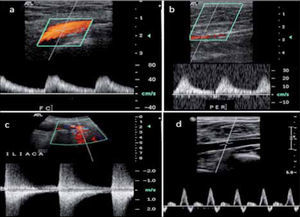

cPulso Tardus Parvus DistalCuando la estenosis en más severa, mayor de 70%, y tenemos un vaso distensible, la curva hacia distal disminuye su velocidad y pendiente de aceleración, lo que se denomina curva tardus-parvus (fig 10b).

a.- Curva de baja resistencia en Arteria femoral común b.- Curva tardus pardus en peronea del mismo paciente c.- Estos hallazgos nos obligan a buscar una estenosis a nivel proximal, constatándose una estenosis iliaca d.- Curva trifásica, de alta resistencia, normal para AFC y arteria peronea del lado contralateral.